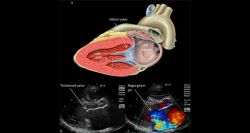

Cœur: opérer mieux, plus vite — l’héritage DeBakey, la trajectoire libanaise

Dans la lumière du bloc, une mini-incision; autour de la table, la Heart Team. En quelques heures, une valve est réparée, une aorte consolidée, un myocarde mis à l’abri. Si le geste paraît plus fluide et moins traumatique, c’est qu’il s’appuie sur un siècle d’innovations et de transmission. Parmi ses architectes, Michael E. ...